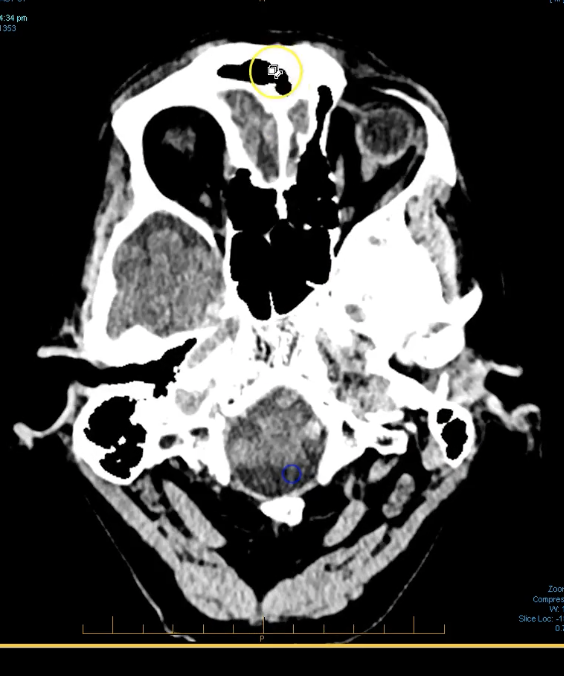

term image

pineal gland- hyperdense. part of endocrine system. secrenes melatonin